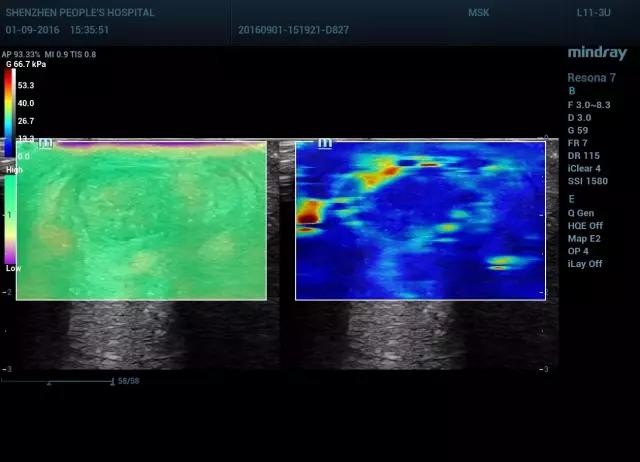

图13 腱周炎剪切波弹性成像(图左 质控图,图右 剪切波成像)